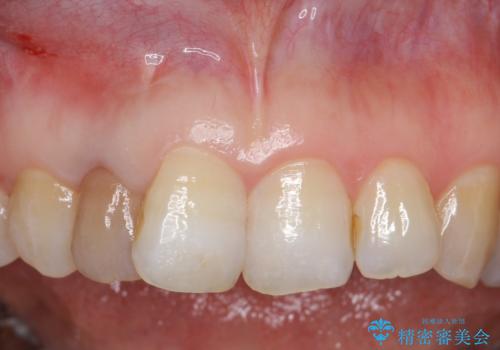

- 右上2番目の歯の変色が気になるといらっしゃった方の症例です。

再根管治療終了後、オールセラミッククラウンによる補綴を行いました。

今回用いたオールセラミッククラウンはジルコニアフレームという白い素材の上にセラミックを盛っているため、審美性が非常に高いのが特徴です。